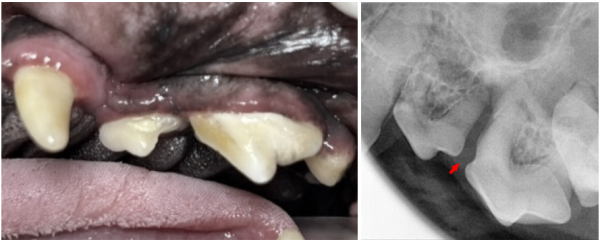

de70cef8385ff32e9ecfc65bf523daeb_1766380431_8105.png

우측 어금니에서는 육안으로

치주염과 치조골 소실이 뚜렷하게 보였습니다.

방사선상 107·108·110번 치아는

· 치조골 50% 이상 소실

· furcation involvement(화살표) Class 3 이상

이 경우 강아지 치아 보존이 매우 어렵기 때문에 발치 후

봉합이 가장 안전한 선택이었습니다.

de70cef8385ff32e9ecfc65bf523daeb_1766380467_5243.png

반면 좌측 어금니는 상황이 다르게 나타났습니다.

207번 치아 distal root와

208번 치아 mesial root 부위에서

치조골 소실은 있었으나,

· 치조골 손실 50% 미만

· 치아 유동성 없음

· furcation involvement 없음

즉, 강아지 치아를 살릴 수 있는 조건이었고,

보호자님과 상의 후 발치 대신 GBR/GTR 보존치료로 결정했습니다.